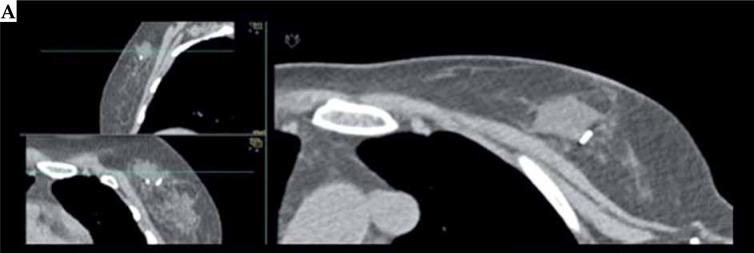

Breast brachytherapy (BB) represents an important radiation therapy modality in modern breast cancer treatments. Currently, BB is mainly used for accelerated partial breast irradiation (APBI), local boost after whole breast radiation therapy (WBRT), and as salvage re-irradiation after second lumpectomy (APBrl). Two multi-catheter interstitial brachytherapy (MIB) techniques can be offered: intra-operative (IOB) and post-operative (POB) brachytherapy. The aim of this article was to summarize current available data on these two different brachytherapy approaches for breast cancer.

乳腺近距离放射治疗(BB)是现代乳腺癌治疗中的一种重要放疗方式。目前,BB主要用于加速部分乳腺照射(APBI)、全乳放疗(WBRT)后的局部加量,以及作为二次保乳手术后的挽救性再照射(APBrl)。可提供两种多导管间质近距离放射治疗(MIB)技术:术中(IOB)和术后(POB)近距离放射治疗。本文的目的是总结目前关于这两种不同乳腺癌近距离放射治疗方法的可用数据。